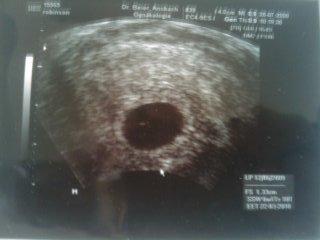

hey maedels, ich hatte ja am dienstag nen FA termin und ich hab total vergessen euch ein bildchen zu zeigen!!! leider konnte man noch nix vom herzschlag sehen aber die fruchhoele is soooooo sehr gewachsen innerhalb von ein paar tagen.. man sieht den dottersack als kleinen weissen punkt.. ich hoffe man kanns erkennen.. is auf som bloeden glanzpapier is so bloed zum abfotografieren.. aber hier und ich mach gleich mal das erste bildchen mit rein damit ihr sehen koennte wie extrem son kleines ding waechst innerhalb von 6 tagen!! LG manu hier mal das neue